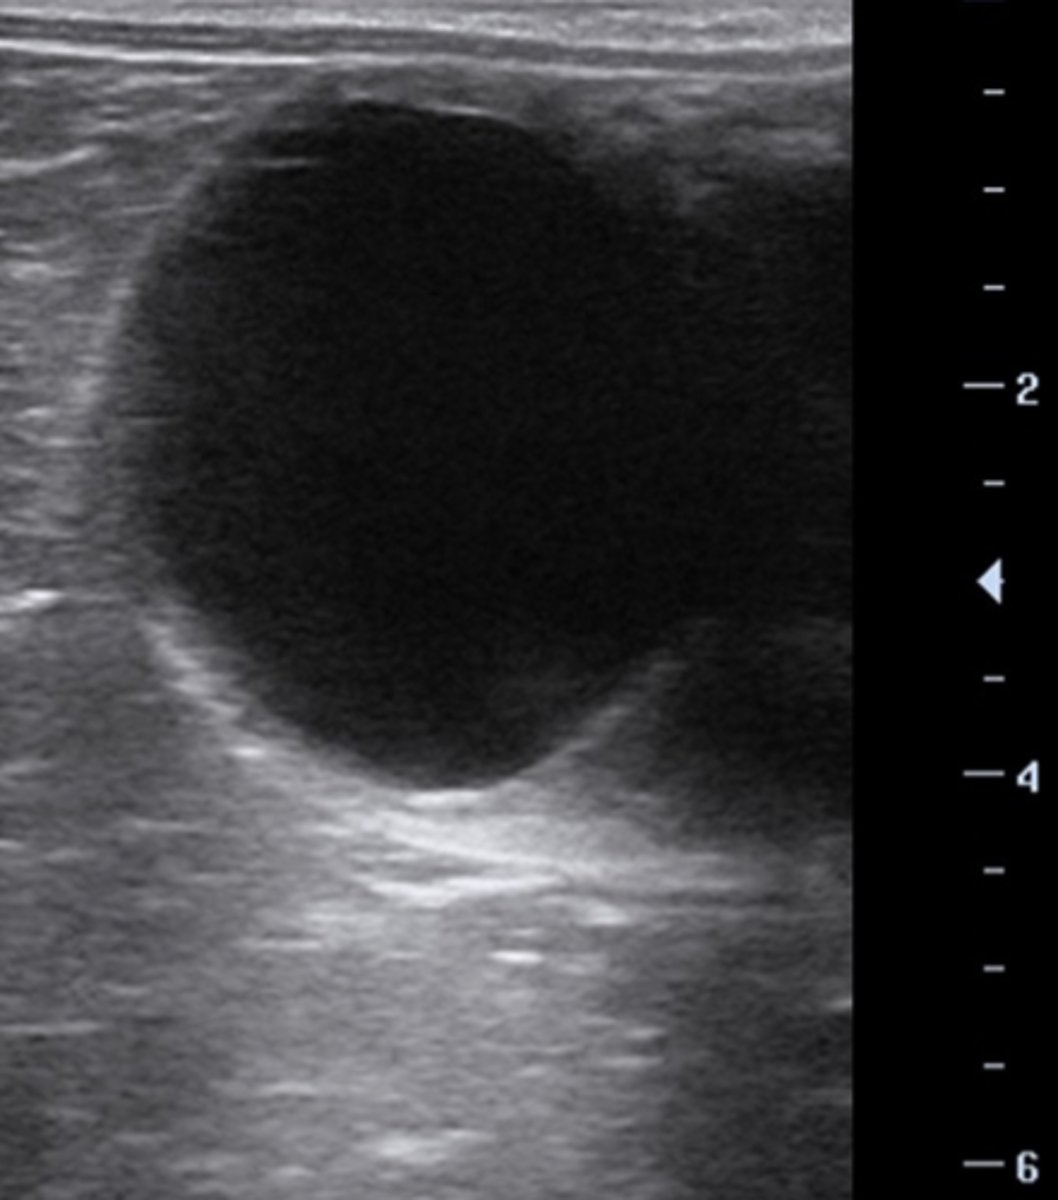

Hoppen har en diøstral follikel og du vil ikke inseminere nu

Ved ultralydsscanning af en hoppes ovarie fandtes denne struktur på 38 mm, et corpus luteum og intet endometrieødem. Hvilken af følgende muligheder vil du vælge?

- Du bestiller sæd og inseminerer hurtigst muligt.

- Hoppen har en haemorrhagisk follikel og du venter 21 dage med at inseminere

- Hoppen har en diøstral follikel og du vil ikke inseminere nu

- Du giver hCG og inseminerer om 48 timer